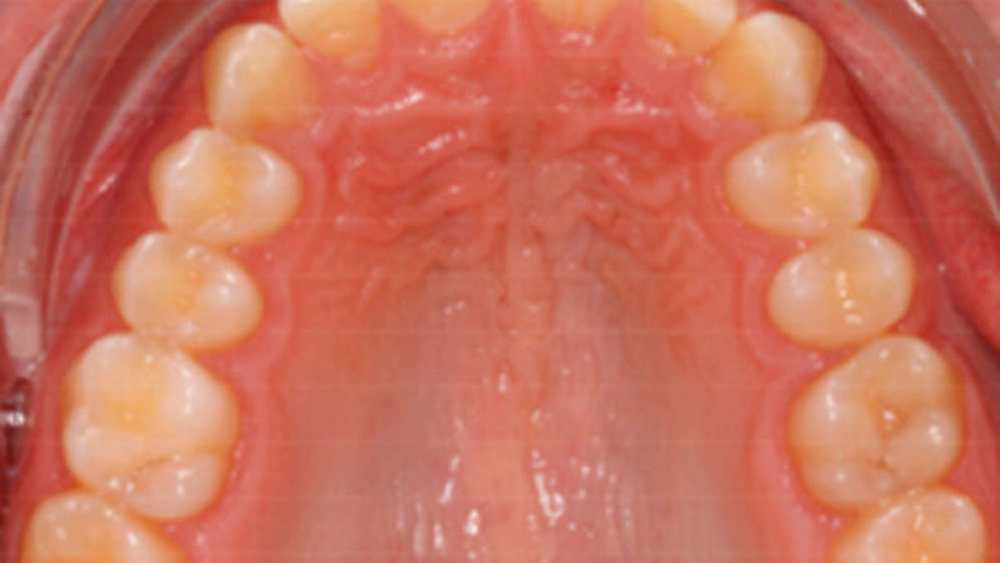

<image seo-title="" alt-text="" aspect-ratio="16-9" xlink:href="https://hcms-cms.medtrix.group/zm/hcms/v3.1/entity/pictures/152337" xlink:role="censhare:///service/masterdata/asset_rel_typedef;key=actual."/>

Abb. 7: Finale Situation: a und b: Das frontale extraorale Erscheinungsbild beim Lächeln und die intraorale Aufnahme zeigen die harmonischen mesio-distalen Breitenverhältnisse im OK-Frontzahnbereich, wobei bei gezielter Betrachtung lediglich der leicht niedrige Gingivaverlauf der an 3er-Position stehenden OK-4er auffällt. c: Die Panoramaschichtaufnahme zeigte eine physiologische Angulation der mesialisierten Eck- und Seitenzähne. d: Die rechte Lateralansicht auf die Zahnreihen demonstriert über drei Jahre nach Therapieabschluss eine stabile und satte Okklusion. e: Die Aufsichtsaufnahme demonstriert die Langzeitstabilität des Lückenschlusses im OK. | Bernd G. Lapatki